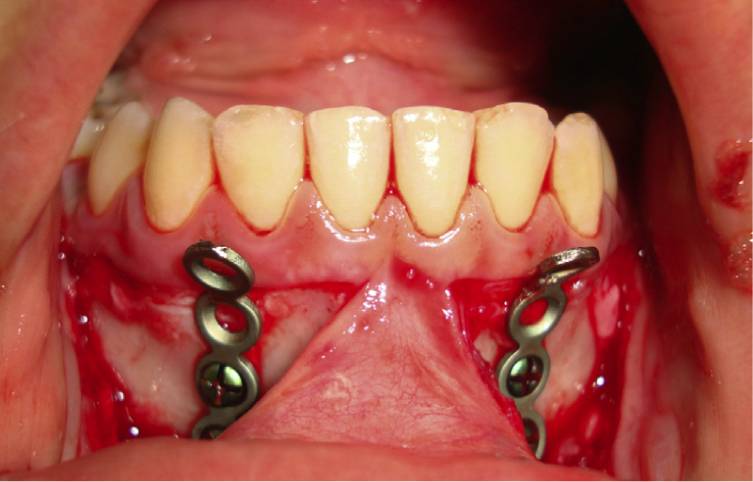

Depuis quelques années, d’autres techniques d’ancrage pour traction du maxillaire ont vu le jour et certains orthodontistes québécois commencent à l’offrir à leurs patients et parents. Vous le verrez peut-être dans votre région. De Clerck et al. (J Oral Maxillofac Surg 2009;67 ;2123-9 et AJODO 2010;138 :577-81) ont démontré l’usage de mini-plaques pour traction du maxillaire. Les mini-plaques étaient placées dans la zone postérieure du maxillaire et antérieure de la mandibule (Figures 1 et 2). Cette approche permet de tracter le maxillaire de patients dont les probabilités de réussite par MF sont réduites i.e. des patients en fin de dentition mixte et début de dentition permanente. Plus récemment, Elnagar et al. (AJODO 2016;150 :751-62 et AJODO 2017;151 :1092-106) ont comparé l’effet de la traction du maxillaire à partir de mini-plaques soit à partir d’un MF (Figure 3) ou d’élastiques de classe III ancrés sur des mini-plaques à la mandibule (Figure 4). Ils ont démontré une différence de mode d’action entre les deux options de traction. La traction partant de mini-plaques au maxillaire vers un MF (Figure 2) a montré une plus grande rotation horaire de la mandibule et une lingualisation des incisives inférieures que la technique sans MF dans laquelle les élastiques de classe III sont portés de mini-plaques maxillaire à des mini-plaques mandibule. Il est intéressant de noter une diminution de l’angle du plan mandibulaire dans le groupe mini-plaques et élastiques sans usage du MF. Cette technique nécessite malheureusement des interventions chirurgicales sous anesthésie générale , la plupart du temps deux, une pour l’installation des mini-plaques au maxillaire et une autre pour la mandibule. Il en faudra une troisième pour la dépose des mini-plaques. Les adeptes de cette technique se justifient par une meilleure collaboration aux élastiques de classe III qu’au port du MF. Ils rappportent un avancement maxillaire de 2.8 à 5.2 mm selon les études. Les mini-plaques permettent de limiter l’ouverture de l’angle du plan mandibulaire et de traiter dans un groupe d’âge un peu plus avancé i.e. plus de 12 ans, malgré que l’âge moyen des patients de leurs etudes était de 12.24 plus ou moins 1 an. Les traitements par mini-plaques montrent moins de glissement dentaire des dents sur l’arcade et plus de mésialisation de tout le maxillaire. Les études ne démontrent pas de changement transverse au maxillaire donc on n’exclue pas la possibilité d’expansion palatine avant ou durant le traitement par mini-plaques. Il n’existe à ce jour, à ma connaissance, aucune évidence à long terme sur la stabilité de la correction (Figures 5 et 6).

Figure 2. Mini-plaques à la mandibule